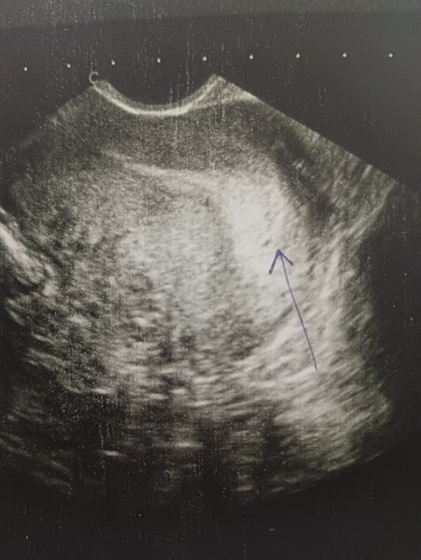

Сходила на УЗИ, ещё больше расстроилась, врач конкретного ничего не сказала, отметила вот точек на снимке говорит в разных ракурсах она ее тут видит но утверждать что я беременна не может((( в правом яичнике жёлтое тело 22 мм и и в заднем своде незначительное количество свободной жидкости, я короче ничего не поняла, девочки кто в этом разбирается разъясните мне пжл(((

А вообще смотрю на точку, похоже на беременность ?

Желтое тело отличное, эндометрий не могу разобрать сколько, мелко очень… Пожелаю вам удачи! УЗИ через неделю повторите, желательно у этого же спеца))

Ну тут беременность.Точка прямо в середине эндометрия.Поздравляю ))